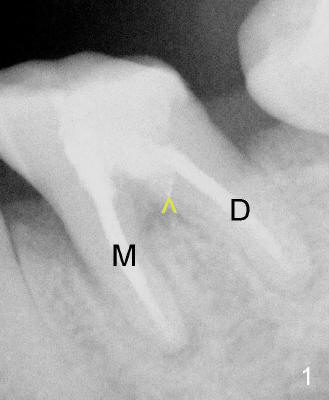

- Dry the canal system with paper points and isolate the perforation

(Fig.2: >)